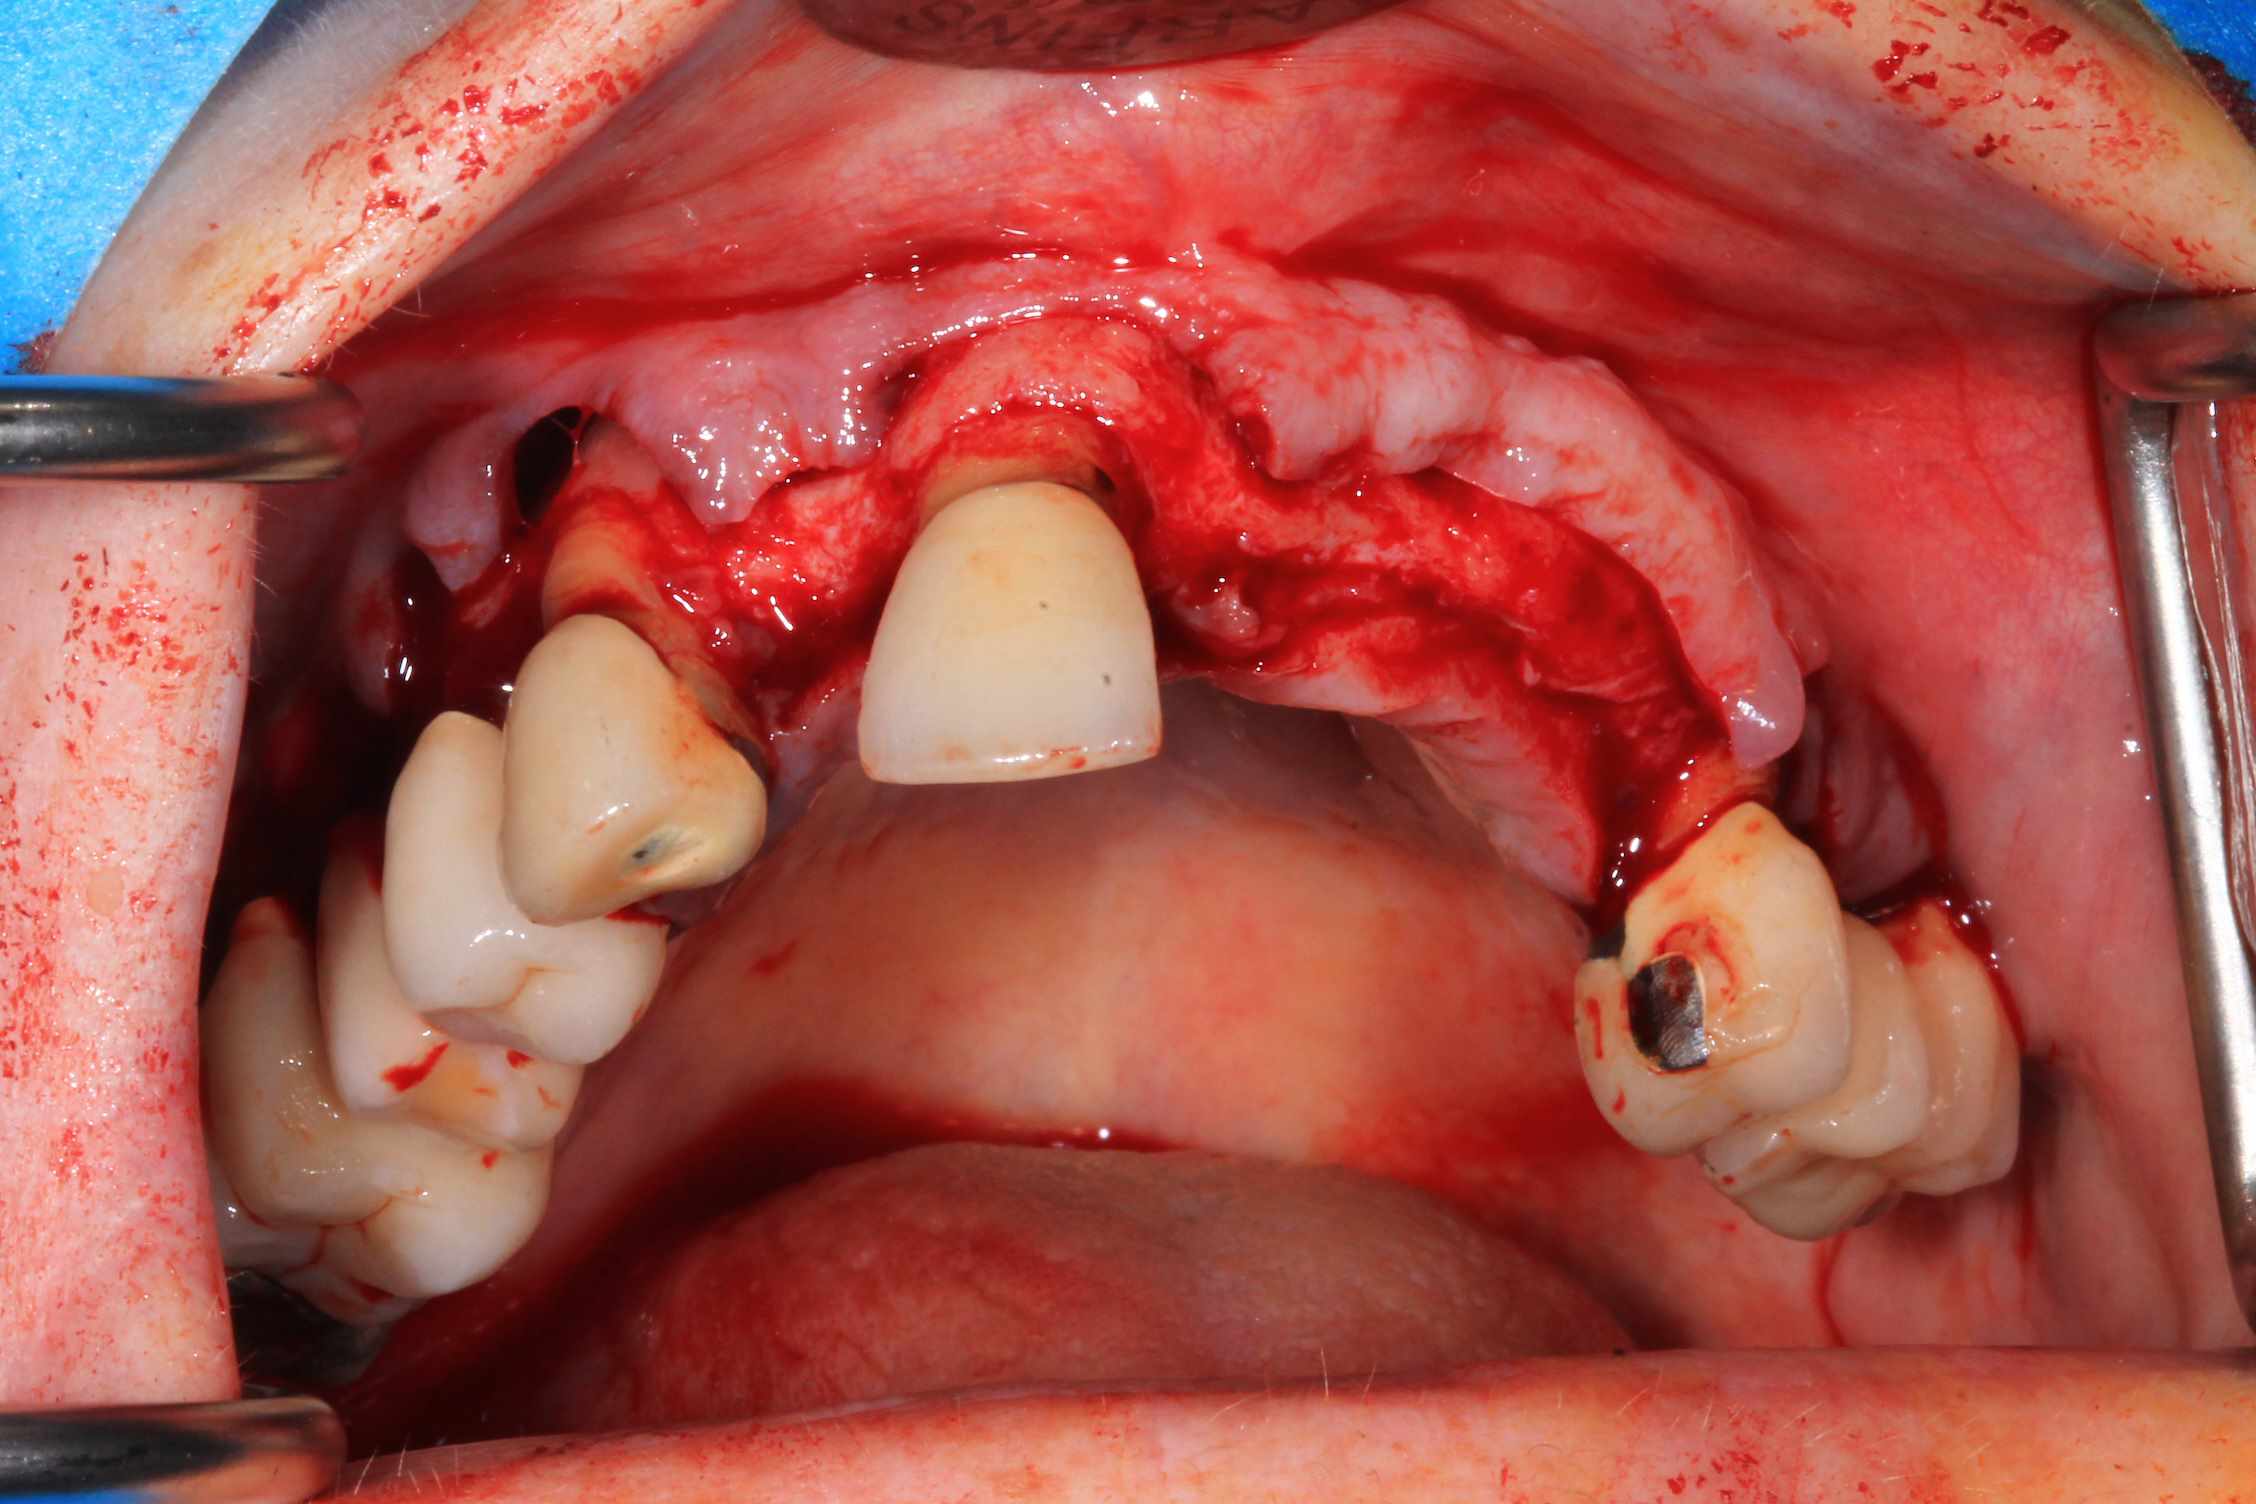

Le cas N°2 en images reelles :)

Guide métal avec support clavette, os assez fin : il est prévu un sticky bone complet : donc : lambeau avant extraction, positionnement du guide base et forage des clavettes, positionnement du guide implant, pose des piliers MU, controle des axes prothétique avec le guide pilier, collage des piliers prov sur le bridge a armature métal, occlusion nickel, sticky bone et PRF, sutures suspendues.